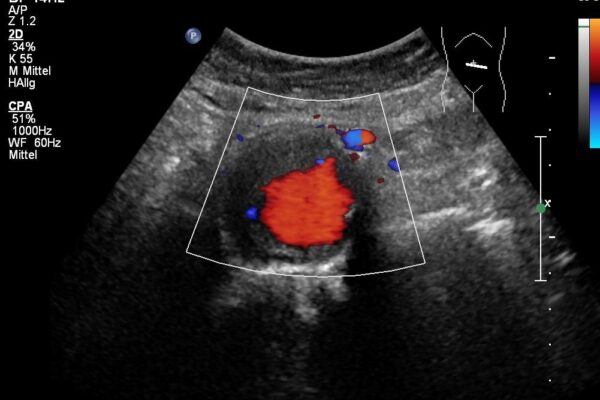

Duplex- und Dopplersonographie

Duplex- und Dopplersonographien sind spezielle Ultraschalluntersuchungen, mit denen Arterien und Venen, also Blutgefässe, beurteilt werden können. Der Schallkopf sendet Wellen in einer bestimmten Frequenz aus, die Wellen werden von den Blutkörperchen und den Gefässwänden in einer veränderten Frequenz reflektiert. Diese Veränderungen der Frequenzen hängen u.a. von der Bewegung der Blutkörperchen ab. Dadurch kann die Richtung des Blutflusses und die Fliessgeschwindigkeit des Blutes bestimmt werden. Dem Arzt ist es dadurch möglich, Einengungen (Stenosen) oder Verschlüsse von Blutgefässen zu erkennen. Die Methode ist völlig risikofrei und eignet sich zur Untersuchung sämtlicher Blutgefässe am Hals, an den Extremitäten (Arme und Beine) sowie im Bauchraum.

- Venenthrombosen an den Beinen (Venenverstopfung durch Blutgerinnsel)

- Arteriosklerose (Gefässverkalkungen durch Ablagerungen von Kalk und Fetten in den Arterien) zB bei den Halsgefässen zur Vorbeugung eines Hirninfarktes